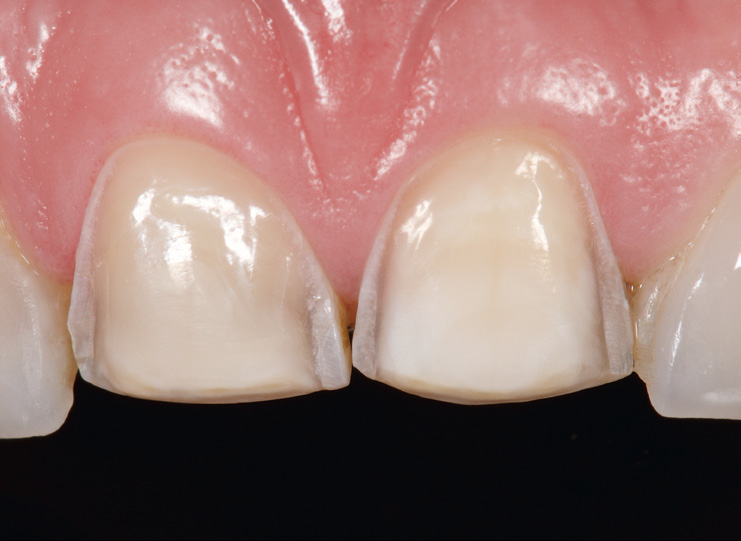

Initial situation. Veneers on teeth 11 and 21 repaired with 3M™ Filtek™ Ultimate Universal Restorative.

Palatal view showing incisal edge crack of veneer on tooth 11.